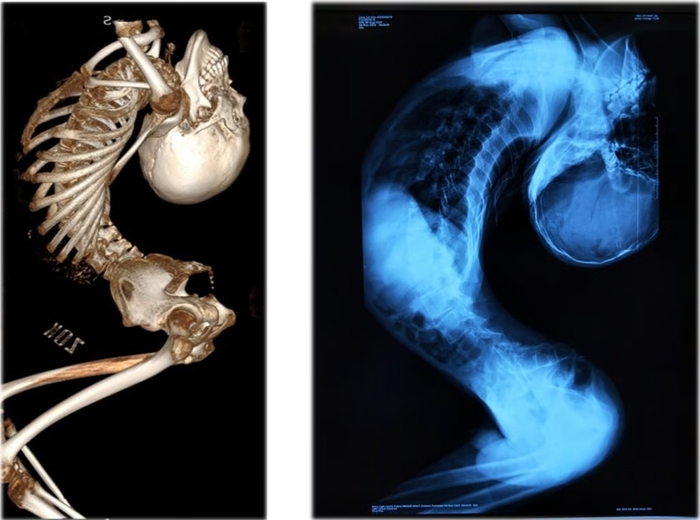

![[전자신문] 180도 허리 꺾인 중국 '폴더 소년' 21년 만에 똑바로 섰다 2 중국 '폴더 소년' 척추 변형 상태. 사진=사우스차이나모닝포스트 캡처](https://img.etnews.com/news/article/2025/08/29/news-p.v1.20250829.b0d033e1489b42c7903bf58e48eed30c_P1.jpg)

2004년 중국 산둥성의 작은 마을에서 태어난 장옌첸은 선천성 근육 질환으로 초등학교 시절부터 목이 점점 뒤로 젖혀지더니 상체가 알파벳 ‘Z’ 모양으로 접히게 됐다. 척추가 심하게 뒤로 젖혀지면서 가슴과 복강이 극도로 좁아지고 장기들마저 좁은 공간에 갇혀 건강이 악화하기 시작했다.

그러나 대학 입학 후에는 상태가 더욱 악화했다. 2023년 5월에는 접힌 몸으로 인해 호흡 곤란이 오기도 했다. 베이징 대형 병원은 희귀 선천성 근이영양증으로 인한 척추 후굴 변형이라는 진단을 내렸다. 최초의 사례이기 때문에 입증된 치료법이 없어 치료에 난항을 겪었다.

2024년 척추 기형 치료로 유명한 량이젠 교수의 치료를 시작하면서 그의 치료 길이 열렸다. 량이젠 교수는 허리뼈, 경추, 고관절, 흉부 뼈를 절단 후 재정렬하는 네 차례의 초고난도 수술은 올해 6월까지 진행됐다. 약 180도로 꺾여 있던 척추는 마침내 바로 섰고, 장옌첸은 매일 6시간의 재활을 통해 걸을 수 있게 됐다.